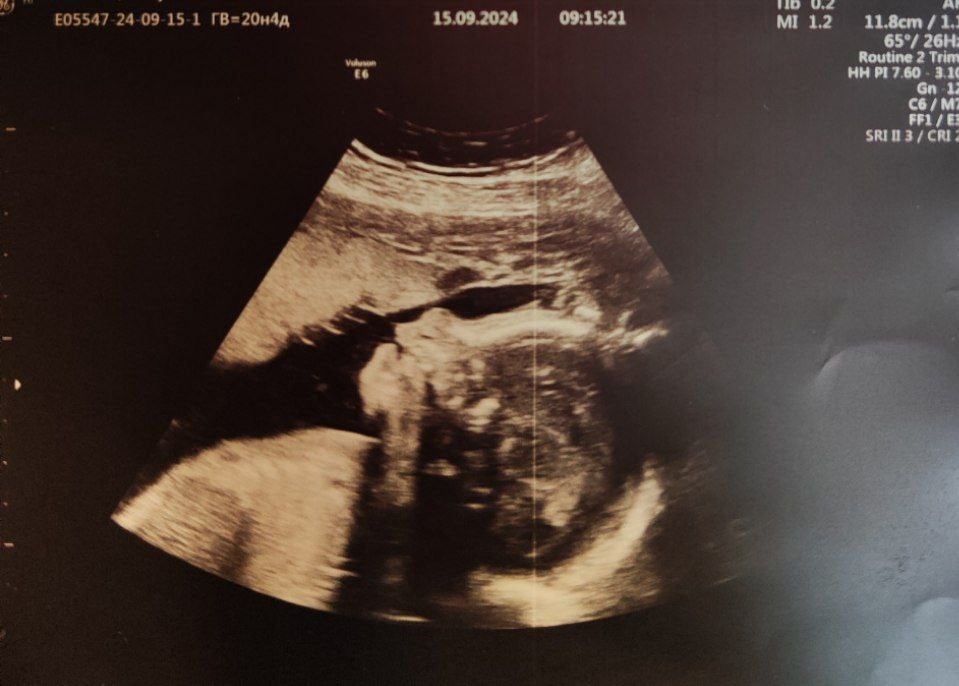

20 недель 4 дня, второй скрининг (15.09.2024)

Масса 471г (98 процентиль, опережение на 2 недели)

БПР 55мм, ОЖ 179мм, ДБ 35мм